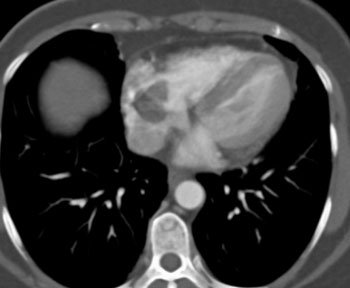

Diagnosis: Left Atrial Myxoma

- 85% are in left atrium attached to atrial septum near fossa ovalis